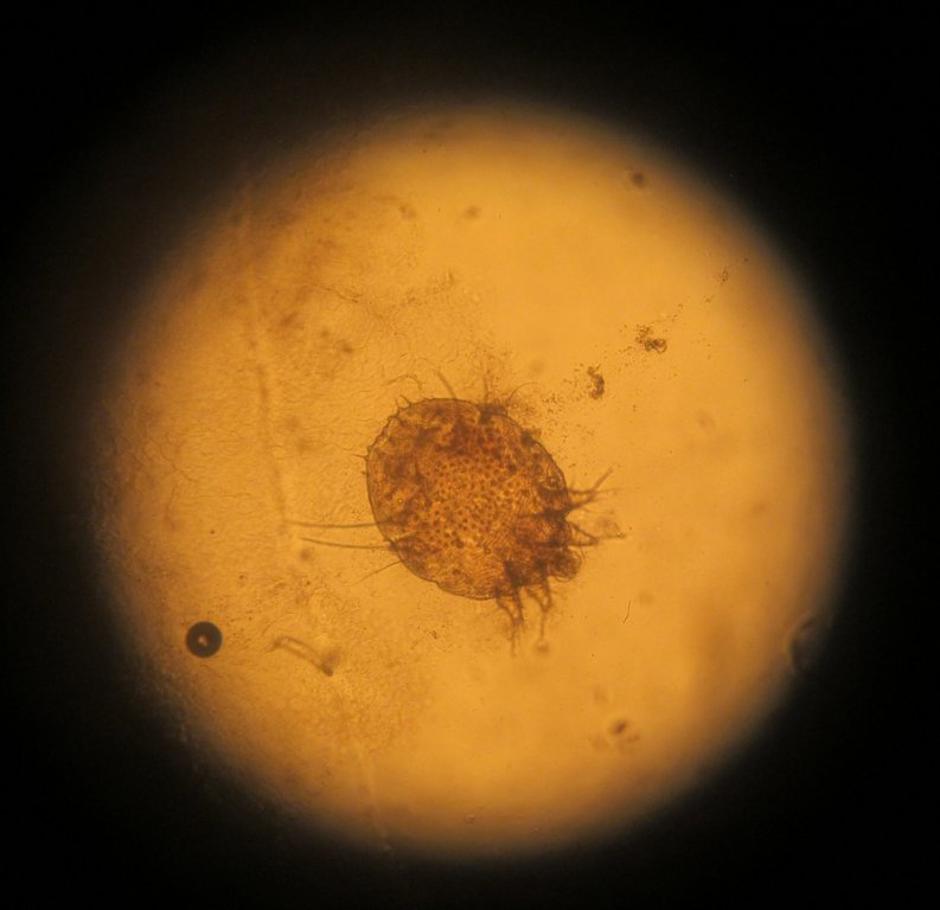

Garje ali srbečica so nalezljiva bolezen, ki jo povzroča pršica, imenovana srbec. Odrasla samica vrta rovčke v povrhnji plasti kože in vanje leže jajčeca. Vrta zlasti ponoči, ko postane koža topla, zato takrat tudi najbolj srbi.

Kožne spremembe najdemo predvsem tam, kjer je koža mehka in tanka (med prsti, notranja stran zapestja, komolec, kolena, okrog popka …). Spremembe na koži so v obliki rožnatih papul, velikosti prosa, s krastico na vrhu. Običajno sta po dve in dve skupaj, kar predstavlja začetek in konec rovčka.